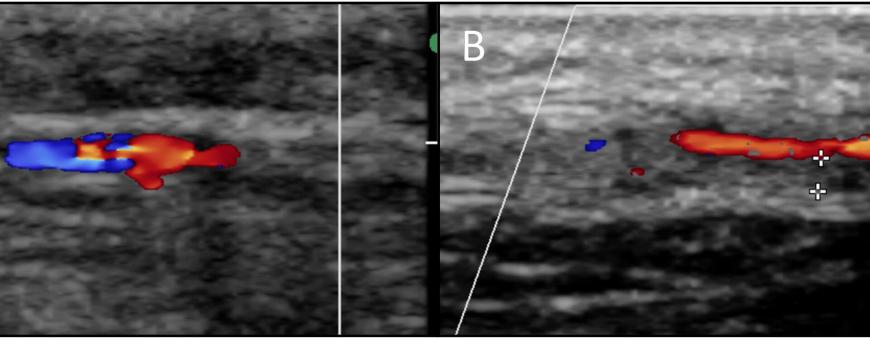

Een 60-jarige patiënte met pijn in de rug en bil onderging een CT-scan van de buik. De voorgeschiedenis vermeldde twee jaar

Een aneurysma van de arteria lienalis is een zeldzame diagnose, zeker bij een jonge, gezonde vrouw. Dit type aneurysma is geassocieerd met onder andere atherosclerose, andere vaatwandziekten zoals bindweefselziekten, (portale) hypertensie en verhoogde viscerale flow. Het exacte ontstaansmechanisme is nog niet bekend. Niet-geruptureerde aneurysmata zijn bijna altijd asymptomatisch. In minder dan 5% van de gevallen zijn er aspecifieke symptomen. Het is dus een diagnose die vaak bij toeval wordt gesteld. Uitstel van de diagnose kan leiden tot het ruptureren van het aneurysma en dit gaat samen met een hoge morbiditeit en mortaliteit. CT-angiografie is het diagnosticum van keuze voor het aantonen van dit aneurysma. Asymptomatische aneurysmata worden nagenoeg altijd behandeld, gezien het risico op ruptuur. Alleen bij ernstige comorbiditeiten van de patiënt is follow-up van het aneurysma te overwegen. Zowel een endovasculaire als een chirurgische behandeling is mogelijk.